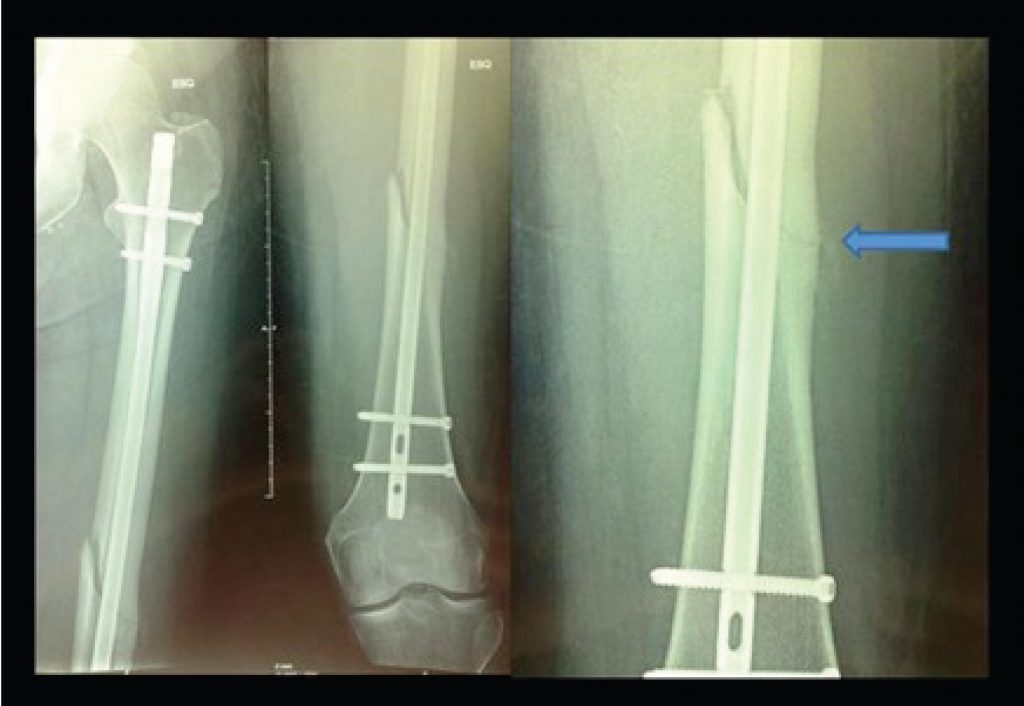

Fraturas diafisárias do fêmur por baixa energia nos pacientes idosos com uso prolongado de alendronato

Fraturas no fêmur proximal ocorrem em mulheres e homens idosos devido a trauma de baixa energia em ossos osteoporóticos. Recomenda-se o tratamento da osteoporose, especialmente com bifosfonatos, para tais fraturas sejam evitadas().

O alendronato foi o primeiro fármaco aprovado pelo Food and Drug Administration (FDA), em 1995, para tratar osteoporose(). Essa droga atua no metabolismo ósseo, ao inibir os osteoclastos, induzir sua apoptose(), elevar a densidade mineral óssea e reduzir a incidência de fraturas osteoporóticas().